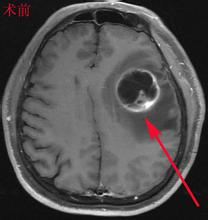

颅内多中心性胶质母细胞瘤1例

脑胶质母细胞瘤少见MRI表现:附11例病例报道